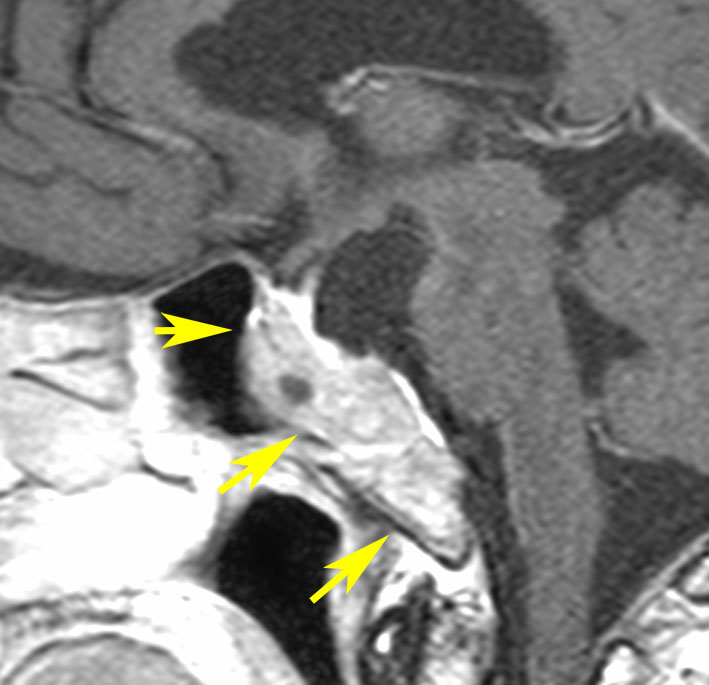

典型的なMRIの画像です

下垂体腺腫のMRIです。両側の視野障害(両耳側半盲)のために手術を受けた患者さんのものです。この腫瘍は非機能性腺腫といってホルモンを出さない腫瘍でした。少し大きめでしたが全部取れて視野の障害はよくなりました。

左の2枚はガドリニウム造影剤を使って写したもので腫瘍の形がよくわかります。右の1枚はT2強調画像と言います。MRIでは撮影の仕方によって見え方が違います。

左は下垂体腺腫(緑の腫瘍)が内頚動脈に挟まれていることを示しています。

中央は手術前の下垂体腺腫で,視神経も正常下垂体も位置はわかりません。

右は手術翌日の画像です。黄色の矢印の先が残した正常下垂体組織です。桃色の矢印の先に視神経(視交叉)がはっきり見えています。術後の一時的な尿崩症がありました。クモ膜が残っているので髄液漏は生じませんでした。でも正常下垂体組織(黄色矢印)も視交叉も腫瘍に圧迫されてペラペラになっていますから,いつもうまく行くとは限りません。